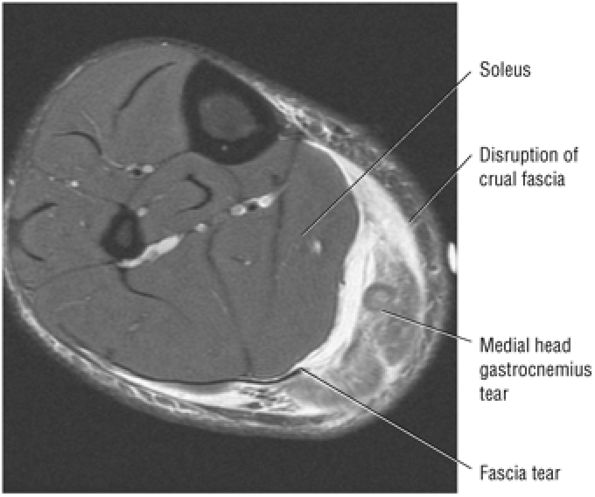

FIGURE 5.128 ● Grade 1 soleus muscle strain secondary to an Achilles rupture. Axial FS PD FSE image.